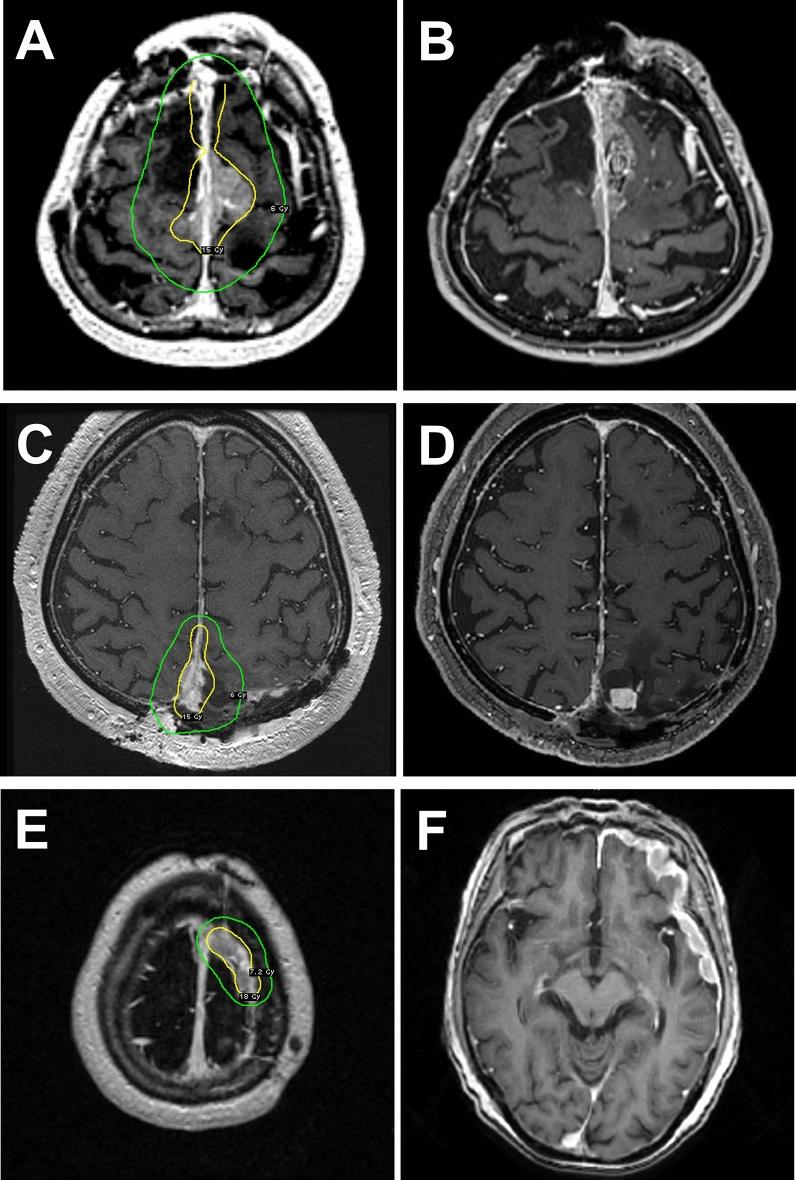

This retrospective study examined 39 patients with atypical meningiomas who underwent SRS over a 10-year study period. Ki-67 LI was categorized into 3 groups: low (< 5%), intermediate (5%-10%), and high (> 10%). Local tumor control rates (LCRs), progression-free rates (PFRs), disease-specific survival (DSS) rates, and adverse radiation-induced events (AREs) were evaluated.

The median follow-up periods were 26 months. SRS was performed at a median prescription dose of 18 Gy for tumors with a median Ki-67 LI of 9.6%. The 3-year LCRs were 100%, 74%, and 25% in the low, intermediate, and high LI groups, respectively (p = 0.011). The 3-year PFRs were 100%, 40%, and 0% in the low, intermediate, and high LI groups (p = 0.003). The 5-year DSS rates were 100%, 89%, and 50% in the low, intermediate, and high LI groups (p = 0.019). Multivariable Cox proportional hazard analysis showed a significant correlation of high LI with lower LCR (hazard ratio [HR], 3.92; 95% confidence interval [CI] 1.18-13.04, p = 0.026), lower PFR (HR 3.80; 95% CI 1.46-9.88, p = 0.006), and shorter DSS (HR 6.55; 95% CI 1.19-35.95, p = 0.031) compared with intermediate LI. The ARE rates were minimal (8%) in the entire group.